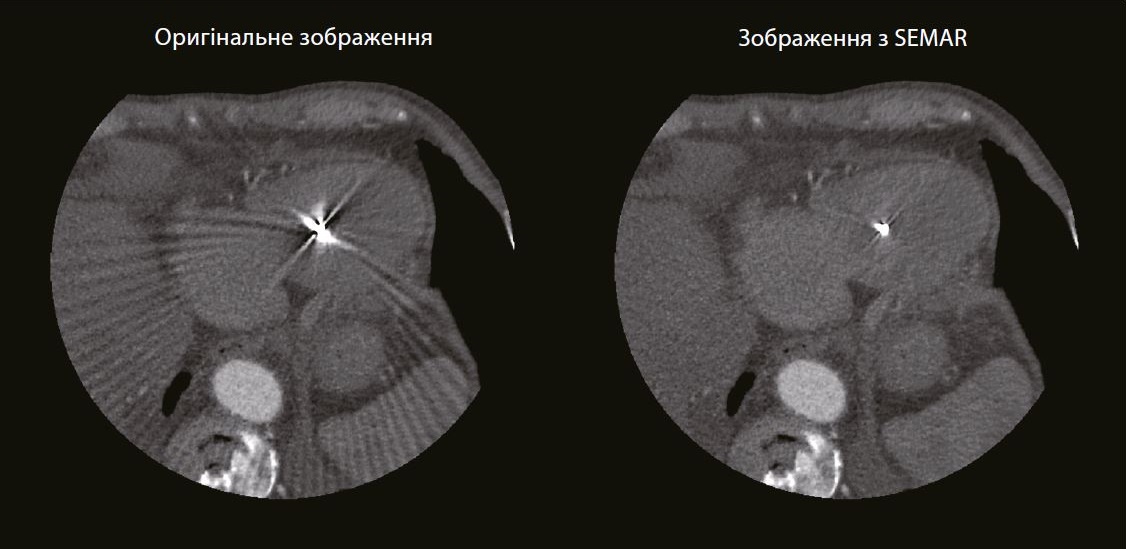

Проксимальна права коронарна артерія частково закрита артефактами. Артефакти, спричинені металевими електродами кардіостимулятора, які більше не видно на реконструкції з використанням SEMAR. Стеноз судини не візуалізується.

EКГ-aдаптований SEMARTM (Технологія зниження артефактів від металу) долає одну з невирішених проблем у КТ візуалізації коронарних артерій у пацієнтів з імплантованими серцевими пристроями, такими як кардіостимулятори та дефібрилятори.

Використовуючи протокол сканування зі звичайним дозовим навантаженням на пацієнта та унікальний процес реконструкції, SEMAR може зменшити металеві артефакти, які інакше могли б заважати візуалізації найближчих коронарних артерій.

У недавньому дослідженні, проведеному Tatsugami et al., діагностичну цінність SEMAR вивчали у пацієнтів з кардіостимуляторами та імплантованими дефібриляторами. Без застосування методів зменшення металевих артефактів 11,7% усіх коронарних сегментів були вражені металевими артефактами та оцінені не були.

У цих пацієнтів реконструкція SEMAR покращила візуалізацію, що дозволило оцінити 97,9% усіх коронарних сегментів